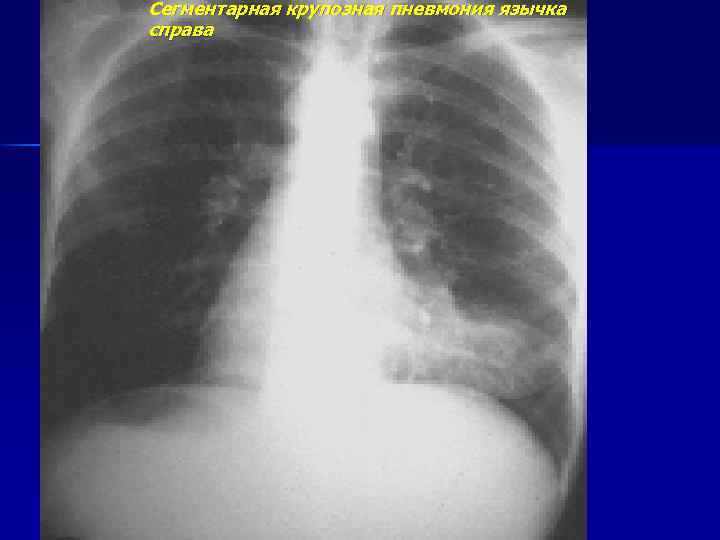

Сегментарная крупозная пневмония язычка справа